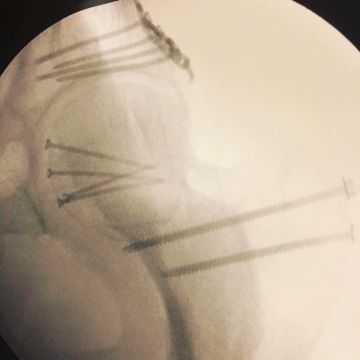

Z kyčelního kloubu je ulomená její část, okolo se nacházejí úlomky pánve a k tomu mám nalomenou stehení kost. Nemocnice Semadan nemá specialisty pro tuto operaci, tak se hned rozjíždí kolotoč hledání specialisty. Ten se našel v sanitkou 2 hodiny vzdáleném Churu. V mezičase vyplňuji tuny a tuny papírů na pojišťovnu. Mám celoroční pojištění Alpenverein a taky evropské pojištění od České pojišťovny. Téměř vše za mě ale vyřizuje sama nemocnice. Nahlásil jsem pouze úraz a absolvoval hovor z rakouského Alpenvereinu. Doktor komunikuje se schvalujícím lékařem za ČP. Po příjezdu do Churu mi v sobotu ráno uznamují, že operace bude v úterý. Dost mi v tu chvíli pomáhá Ivo s komunikací. Seznamují s postupem operace, dostanu asi 10 šroubů, nějaké titanové desky a tak. V podstatě se snažím zjistit, co to všechno znamená, ale nikdo s tímto typem zraněmí nemá moc zkušeností.

Operace trvá 5 hodin. Naštěstí jsem neměl žádné komplikace (krom těch kosmetických) , dostal jsem pár snímků se šrouby. Vnější úpravu dobře vidím sám. Druhý den chodítko, třetí den berle a chodit. Po týdnu od operace a po převozu do hradecké fakultky jsem zažil skutečné cestování v čase. Nejmodernější věcí místní chirurgie jsou patrně plastová okna, jinak prostředí, atmosféra i přístup personálu jak z černobílého filmu.